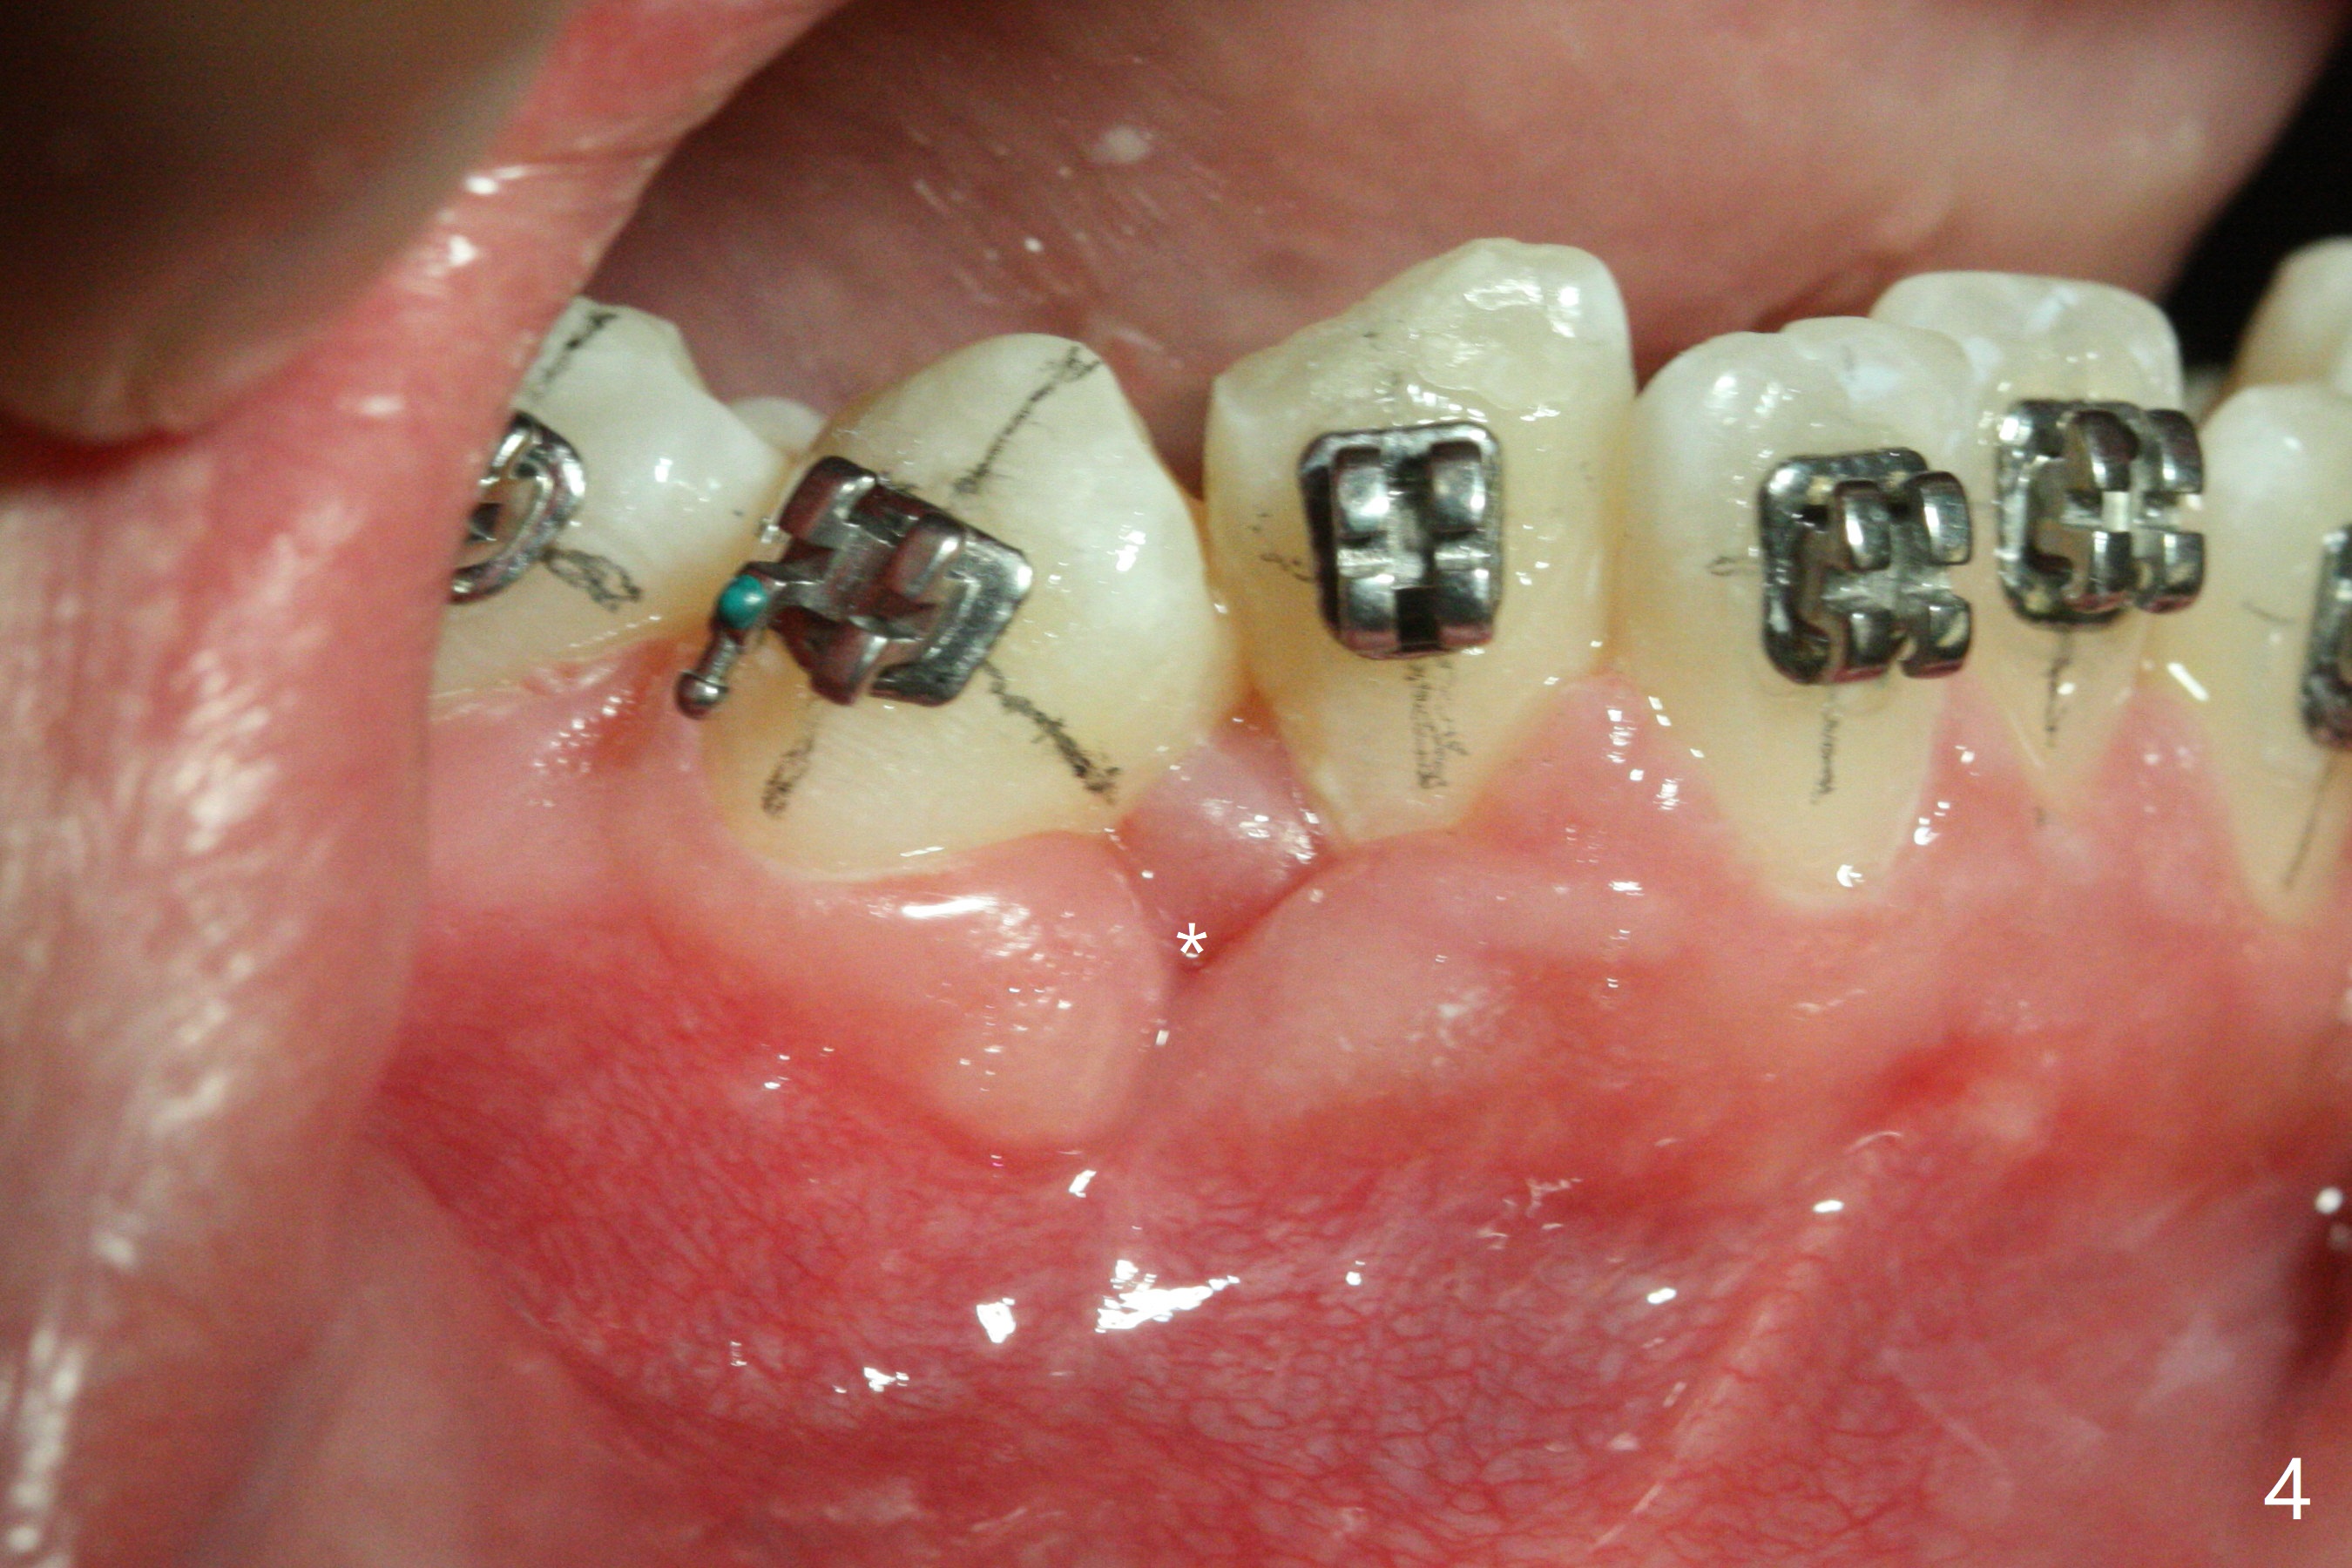

The socket of LR3 heals 2 months post extraction (Fig.4: *). LR4 is bracketed as LR3. Brackets and Bands are placed with 14 niti wires (Fig.5,6).